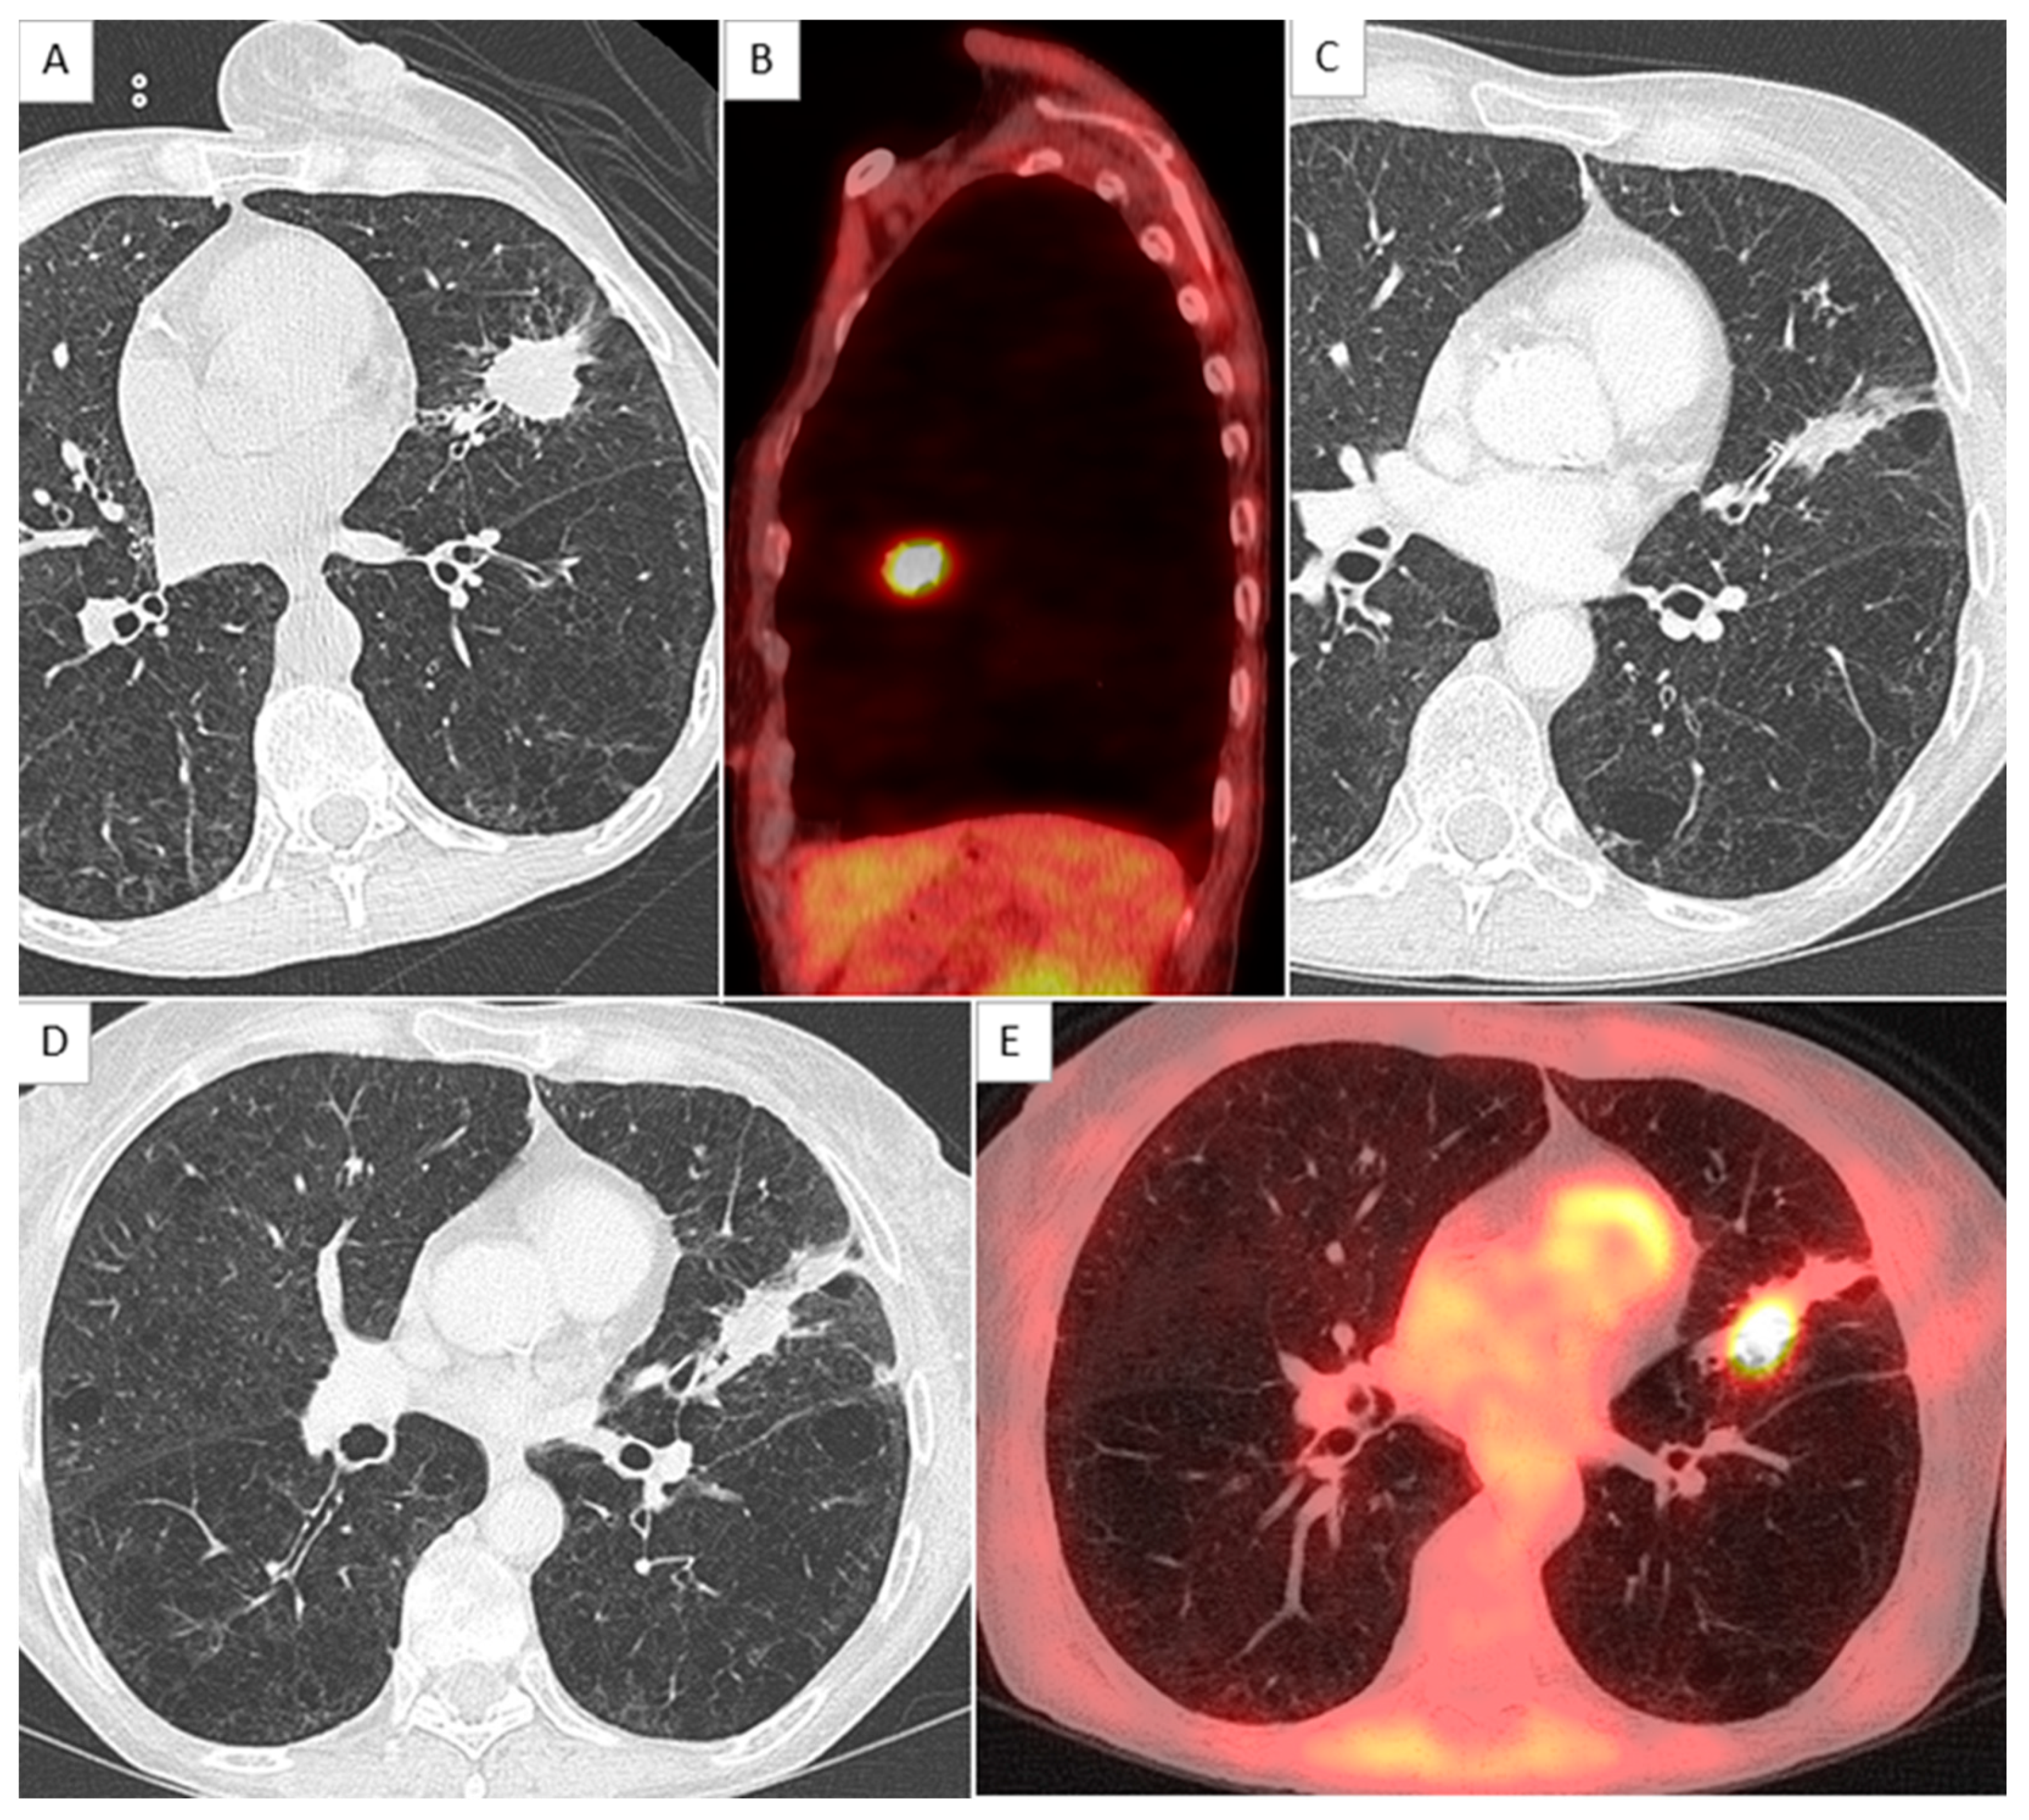

2.4. CT Scan Monitoring

2.5. Local Relapse Definition

- Chassagnon, G.; Martini, K.; Giraud, P.; Revel, M.P. Radiological assessment after stereotactic body radiation of lung tumours. Cancer/Radiothérapie 2020, 24, 379–387. [Google Scholar] [CrossRef]

- Vulquin, N.; Feutray, S.; Peignaux-Casasnovas, K.; Humbert, O.; Créhange, G.; Truc, G.; Maingon, P.; Martin, E. Radiological evaluation of the tumour response after lung stereotactic radiotherapy. Cancer Radiother. J. Soc. Fr. Radiother. Oncol. 2014, 18, 414–419. [Google Scholar]

- Kato, S.; Nambu, A.; Onishi, H.; Saito, A.; Kuriyama, K.; Komiyama, T.; Marino, K.; Araki, T. Computed tomography appearances of local recurrence after stereotactic body radiation therapy for stage I non-small-cell lung carcinoma. Jpn. J. Radiol. 2010, 28, 259–265. [Google Scholar] [CrossRef]

- Huang, K.; Dahele, M.; Senan, S.; Guckenberger, M.; Rodrigues, G.B.; Ward, A.; Boldt, R.G.; Palma, D.A. Radiographic changes after lung stereotactic ablative radiotherapy (SABR)—Can we distinguish recurrence from fibrosis? A systematic review of the literature. Radiother. Oncol. J. Eur. Soc. Ther. Radiol. Oncol. 2012, 102, 335–342. [Google Scholar] [CrossRef] [PubMed]

- Huang, K.; Senthi, S.; Palma, D.A.; Spoelstra, F.O.; Warner, A.; Slotman, B.J.; Senan, S. High-risk CT features for detection of local recurrence after stereotactic ablative radiotherapy for lung cancer. Radiother. Oncol. J. Eur. Soc. Ther. Radiol. Oncol. 2013, 109, 51–57. [Google Scholar] [CrossRef] [PubMed]